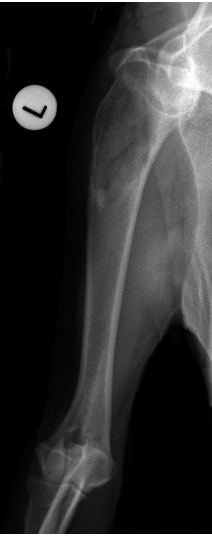

what radiographic view of the humerus is shown?

lateral view

what position will we put the animal in for a caudal-cranial view of the humerus?

dorsal recumbent position with the forelegs extended cranially

caudo-cranial view

what position will we put the animal in for a cranio-caudal view of the humerus?

dorsal recumbent position with the forelegs extended caudally

cranio-caudal view